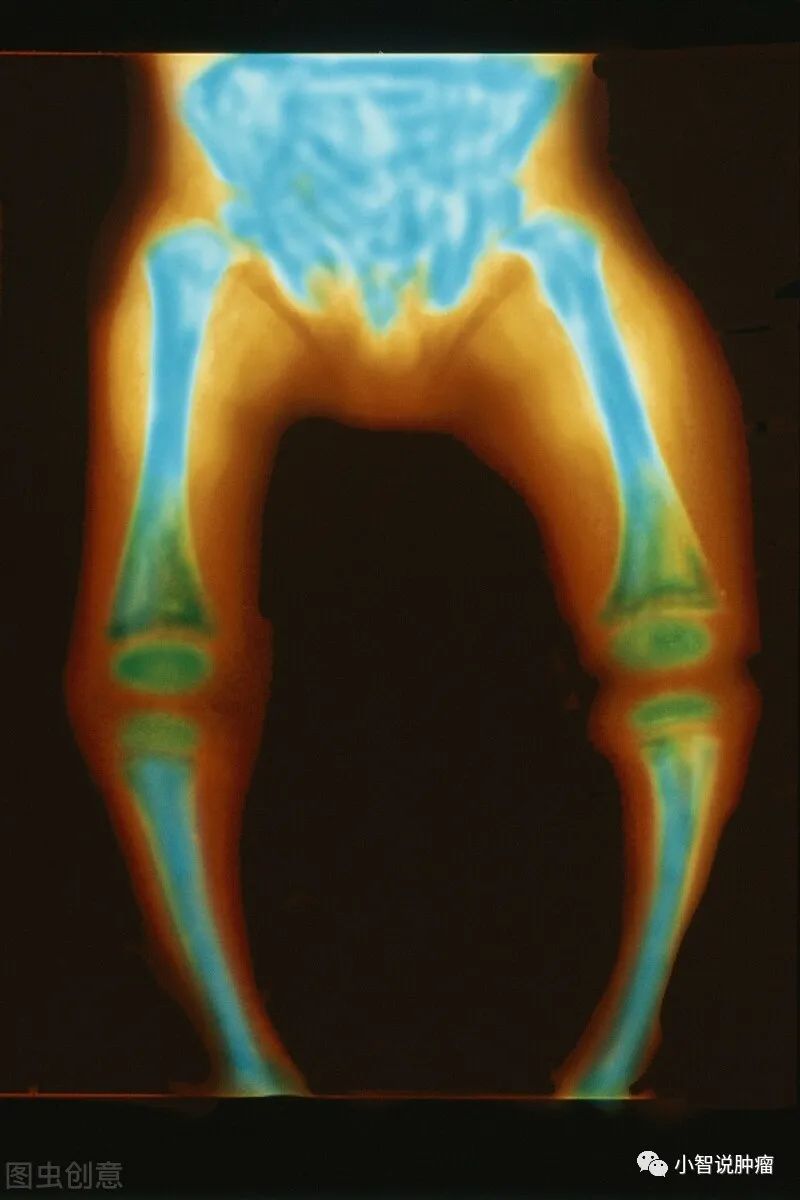

佝偻病,

全称为维生素D缺乏性佝偻病。

光看全名,

我们不难猜测,

关于佝偻病的发生,

“维生素D”指定脱不了干系。

不错,

佝偻病的发生,

主要是缺乏维生素D导致的。

但当 没有足够的维生素D时, 会无法使充足的钙、磷进入软骨, 导致软骨钙化不全, 软骨在干骺端堆积,一系列佝偻病体征就来了。